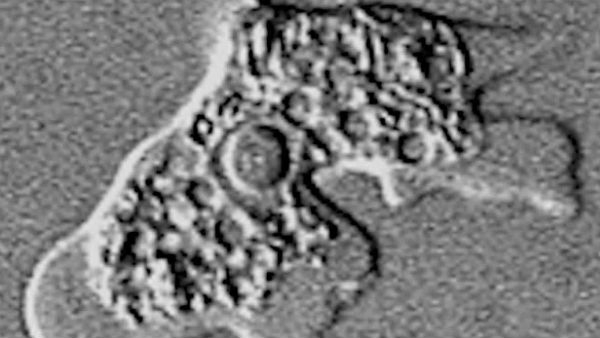

అమీబా నాగ్లేరియా ఫౌలేరి అనే సూక్ష్మ జీవి ఉన్న నీటిని తాగడం వల్ల ఆరేళ్ల బాలుడు సెప్టెంబర్ 8న మరణించాడు. ఆ అమీబా బాలుడి శరీరంలోకి వెళ్లిన తర్వాత లోపల మొత్తం ఇన్ఫెక్షన్ చేసింది. దీంతో అతడు ప్రాణాలు వదలాడు. ఈ ఘటన స్థానికంగానే గాక, రాష్ట్ర వ్యాప్తంగా కలకలం రేపింది.

కాగా, ఆ అమీబా మొదట నాసిక పొరల ద్వారా శరీరంలోకి ప్రవేశించి ఆ తర్వాత మెదడులోకి ప్రవేశిస్తోంది. అనంతరం అమీబా మానవ మెదడుపై దాడి చేయడం మొదలుపెడుతుంది. దీంతో తీవ్రమైన తలనొప్పి, హైపర్థెర్మియా, మెడ నొప్పి, వాంతులు, తర్వాత మైకము, విపరీతమైన అలసట, గందరగోళం, భ్రాంతులు లాంటివి మొదలవుతాయి.